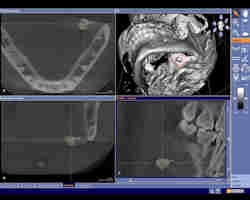

Cone-beam CT dataset showing a slightly overaverage size salivary calculus of 7-8 mm in the left submandibular gland area in the axial (upper left), coronal (lower left), and sagittal (lower right) view. Maximal diameters were measures using the visualization software tools. In the 3D reconstruction (upper right), the reformatted 3D salivary calculus is visualized and marked with a red circle. All images courtesy of Timo Dreiseidler, M.D., D.M.D., University of Cologne. |